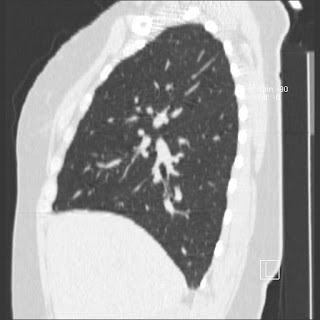

New CT images (without contrast) for 40 year old female with silicone breast implants. Formal diagnosis is expected soon. Images from 2010 can be seen here http://radiology-images.blogspot.com/p/40-year-old-female-silicone-implants.html